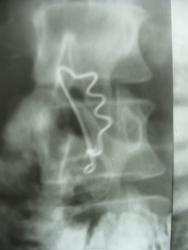

на данное исследование в поликлинике направлена в связи с анемией (незначительная). сам кишечник ни чем не отличился, все в норме, внимание привлекла "булавка", она  двигается при дыхании пациентки. в карточке нашли запись: состояние после кава клипирования (2005) в инфраренальном отделе по поводу ТЭЛА мелких ветвей в послеродовом периоде.это может быть та самая "клипса"? сама пациентка ничего не помнит и ответить не смогла.

клипирование может так  выглядеть ?

Проекционно инородное тело в проекции НПВ, для локализации необходима боковая проекция на первый раз или КТ.

нет  нет...заколка на халатике  исключена. все проверили. во всех сторон осморели и раздели.

и, конечно, сразу опросили насчет глотала ли что-то в прошлом. ответ отрицательный.

это редко проводимые операции КАФАФИЛЬТРАЦИЯ - хирургическое предотвращение попадания тробов из вен нижних конечностей и таким образом предотвращаются попадания их в жизненно важные органы (ТЭЛА, инфаркты и т.д.) более подробно можно посмотреть -

А.Э.Хон, Н.А.Гордеев, В.М.Седов, Ф.В.Баллюзек, Н.А.Шабанова, И.А.Денисова "23-х летний опыт каваклипирования как метода хирургической профилактики ТЭЛА". 22 мая 2009 г.

первое впечатление тоже было на булавку в тонкой кишке, а потом только докопался.

Кстати тут остается интересный вопрос: по идее этот экстравазальный кавафильтр должен стоять перпендикулярно вене, а здесь как?

Наложили то правильно, но защелка располагается со стороны аорты (надо наоборот, если уж пошли на такое варварство), которая пульсирует, м.б. со временем и произошло определенное смещение по оси. Интересно, где-же это в 21 веке делают пликацию нижней полой вены(так называется эта операция). Я думал что такие операции закончились к началу 80-х, когда появились кава-фильтры. Этой больной было показана имплантация временного кава-фильтра с последующим удалением через три недели, теперь в будущем это модет привести к нарушению оттока по венозной системе н-конечностей.